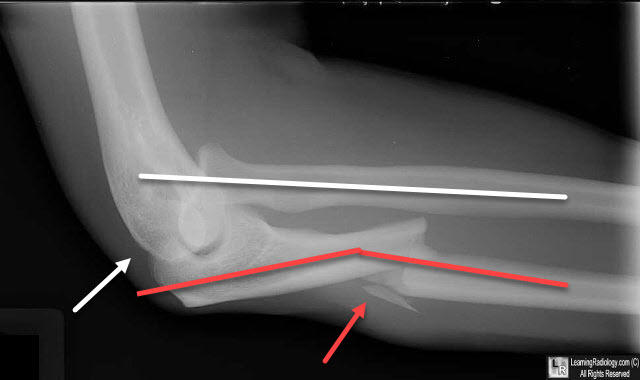

Monteggia Fracture Dislocation. There is a fracture of the mid-shaft of the ulna with angulation leading to shortening (red arrow). A line drawn through the shaft of the radius (yellow line) does not intersect the capitellum (white arrow) indicating a dislocation of the radial head.

Monteggia Fracture Dislocation. There is a fracture of the mid-shaft of the ulna (red arrow) with angulation (red line) leading to shortening of the overall length of the ulna. A line drawn through the shaft of the radius (white line) does not intersect the capitellum (white arrow) indicating a dislocation of the radial head.

- A line drawn longitudinally through the shaft of the radius should intersect the capitellum on all radiographs of the elbow

- The apex of the ulnar fracture almost always points in same direction as radial head dislocation